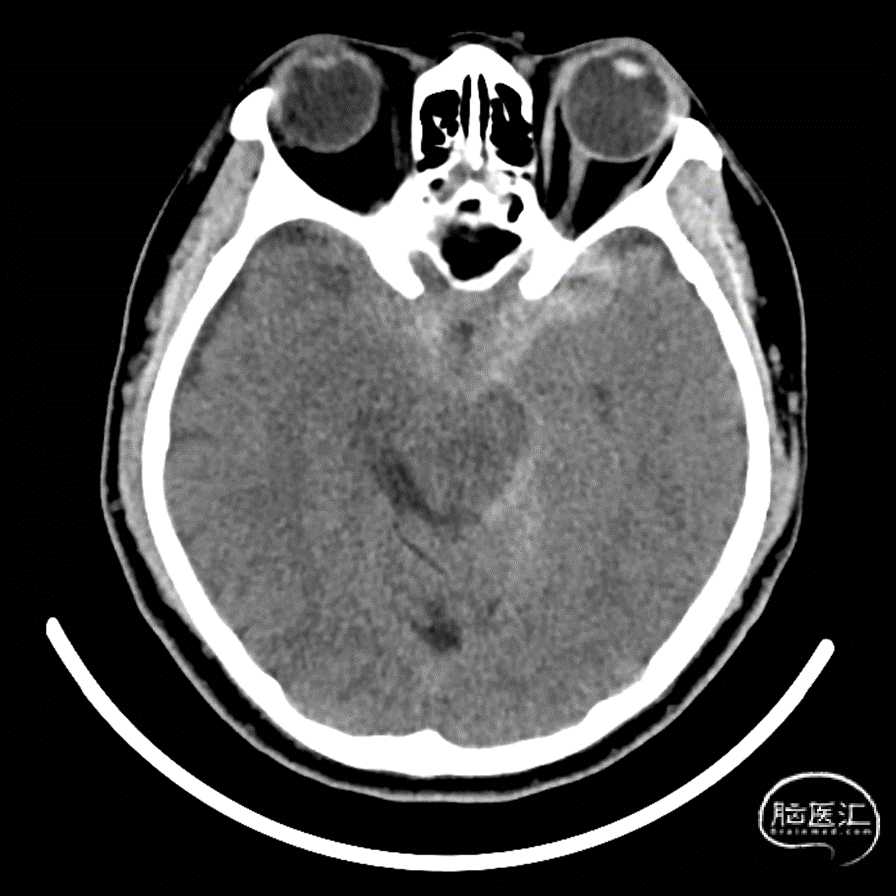

现病史:3小时前突发头痛,急诊行头颅CT提示:自发性蛛网膜下腔出血

头颅CT